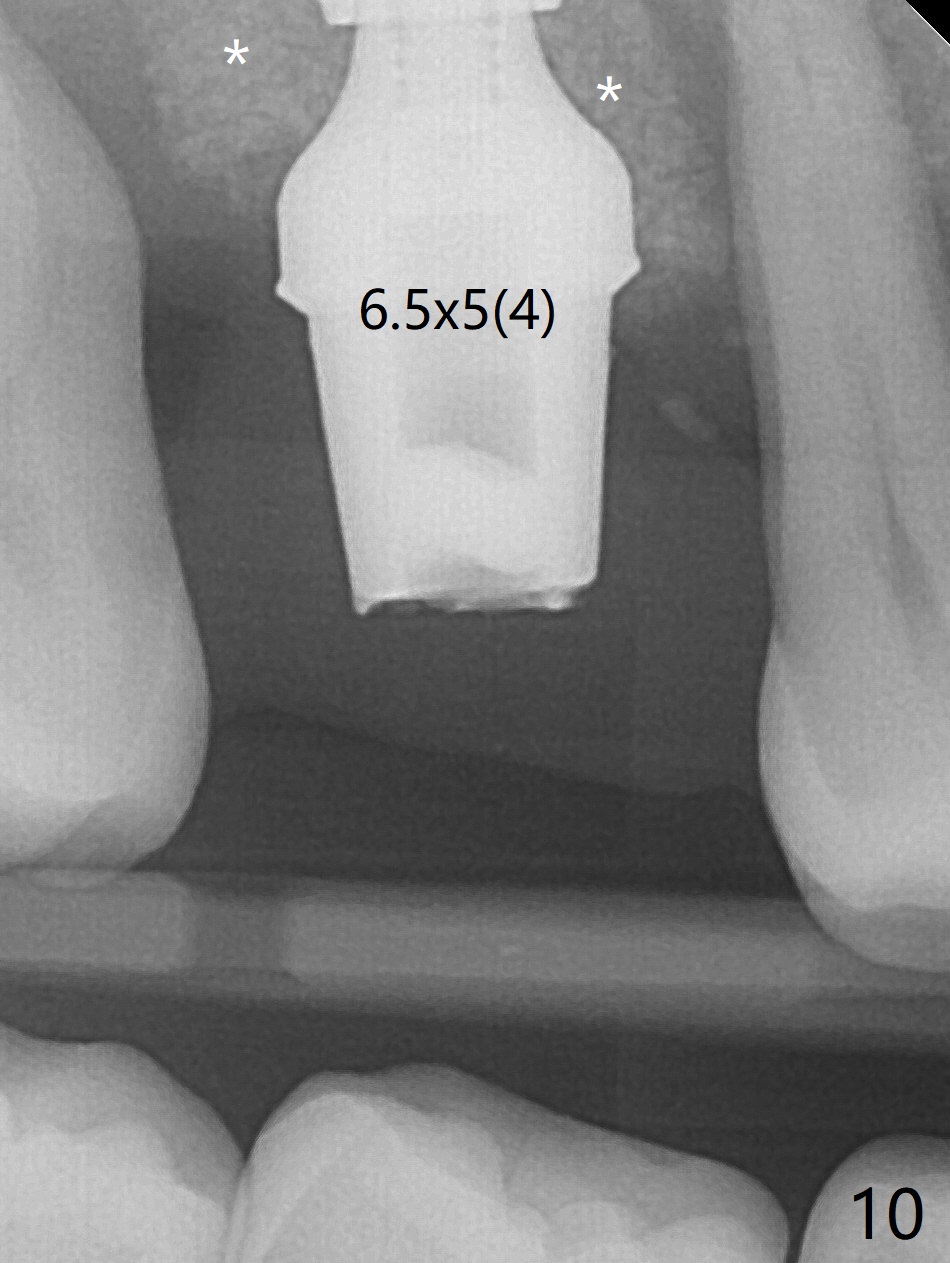

Initial osteotomy depth is 4 mm (Fig.7). The sinus membrane is found to be perforated when the depth increases to 8 mm. The latter could be prevented by taking CT and/or using osteotome. The subsequent osteotomy depth is 5 mm until 4.0 mm in diameter. When the 4.5 mm tap is inserted with initial stability, the shortest implant (8.5 mm, Fig.8 green) will be partially protruded into the sinus and partially exposed in the socket and the cuff of the abutment is expected to be around 6 mm (pink). Since the 5 mm tap achieves primary stability, a 5x8.5 mm implant (following placement of Osteogen plug to repair the perforated sinus membrane) is placed at the level just mentioned (Fig.9). Vanilla Graft mixed with minimal autogenous bone is packed (Fig.10.11 *) before and after insertion of a 6.5x5(4) mm abutment. An immediate provisional as well as a piece of Osteogen plug is fabricated to close the socket gap. The provisional and the abutment are dislodged 1 month postop (Fig.12). The wound has healed. The abutment is reloaded without the provisional. The implant appears to osteointegrate 4.5 months postop (Fig.13); in addition the bone graft seems to have migrated toward the roots of the neighboring teeth (arrows).